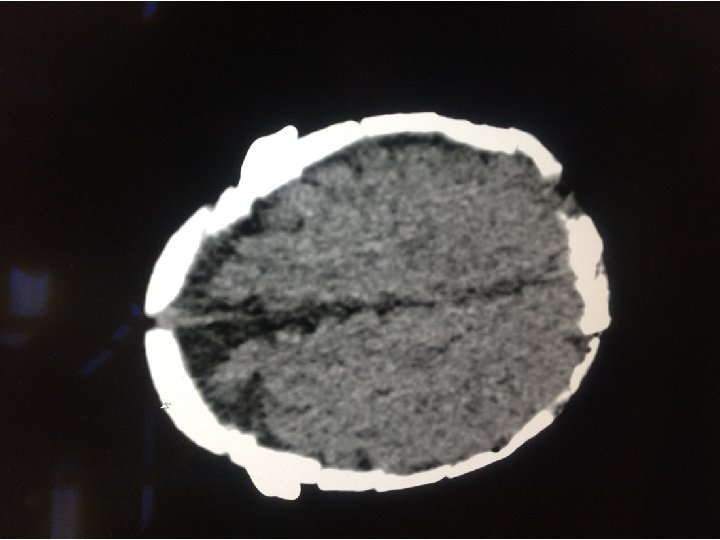

WORK UP • Basic labs • CBC, CMP, PT, INR, PTT • CT Head

SCAPHOCEPHALY • • • Male predominant Most common form Prominent occiput Broad forehead C-sections for cephalopelvic disproportion Does not produce increased ICP or hydrocephalus • Complications occur if two or more sutures close

SOOOO…. . ? • CT shows scaphocephaly, but normal ventricles. • No acute neurosurgical concerns • Primarily sent for nystagmus • Could the nystagmus be anything else?